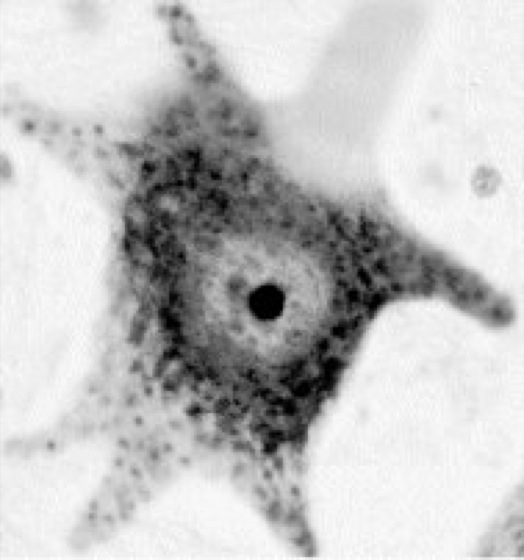

Nissl-Färbung [ben. nach F.A. Nissl], Methode zur Anfärbung (Färbemethoden) vor allem von Nervenzellen mit basischen Anilinfarbstoffen (Methylenblau, Thionin, Toluidinblau [Toloniumchlorid], Kresyl[echt]violett). Diese werden vor allem von den sauren (Phosphat-)Gruppen der DNA und RNA gebunden. So läßt sich neben Zellkern (DNA) und Nucleolus (rRNA) vornehmlich das in den Perikaryen der Nervenzellen reichlich ausgebildete ribosomenbesetzte rauhe endoplasmatische Reticulum (Ergastoplasma) stark anfärben und als sog. Nissl-Schollen oder Tigroid-Schollen selektiv darstellen, während die nahezu ergastoplasmafreien Nervenfasern ungefärbt bleiben ( ä vgl. Abb. ).

Motoneuron aus dem Vorderhorn des Rückenmarks in Nissl-Färbung; rundum 6 Dendritenabgänge und oben der von Nissl-Schollen freie Ursprungskegel des Axons.